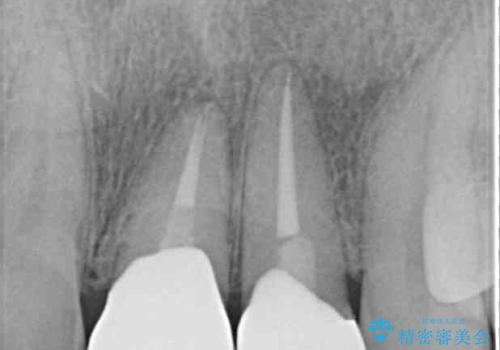

- 下顎前歯が抜けそうとのことで来院された患者様です。

初診の状態ではすぐにでも抜けそうな状態で、インプラントによる補綴治療を行うこととしました。

インプラント治療に際し、前歯の叢生に対する矯正治療を提案したところ、興味を持たれたので、インビザライン・ライトによる矯正治療を行うこととしました。